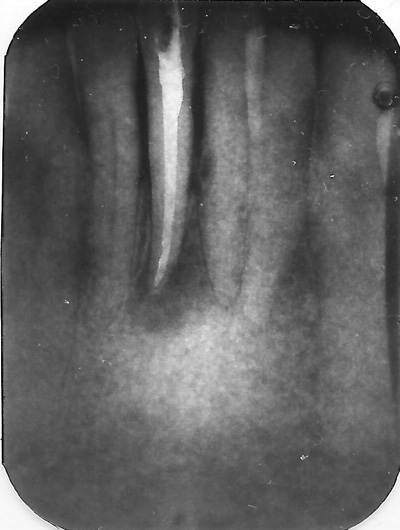

En rodbehandling kan være nødvendig for at fjerne både en levende, betændt eller død bakteriefyldt nerve. Der er en successrate på ca. 80-95% afhængig af tandens tilstand inden behandlingen.

Ved en rodbehandling fjernes nerven og bakterier fra rodkanalen/rodkanalerne.

Når tanden er færdigrenset, desinficeret og symptomfri fyldes rodkanalen/rodkanalerne med et plastisk rodfyldningsmateriale. Herefter laves en tæt plastfyldning.

Efter en observationstid på ca. ½ år anbefaler vi at få en krone sat på tanden, for at undgå den knækker.